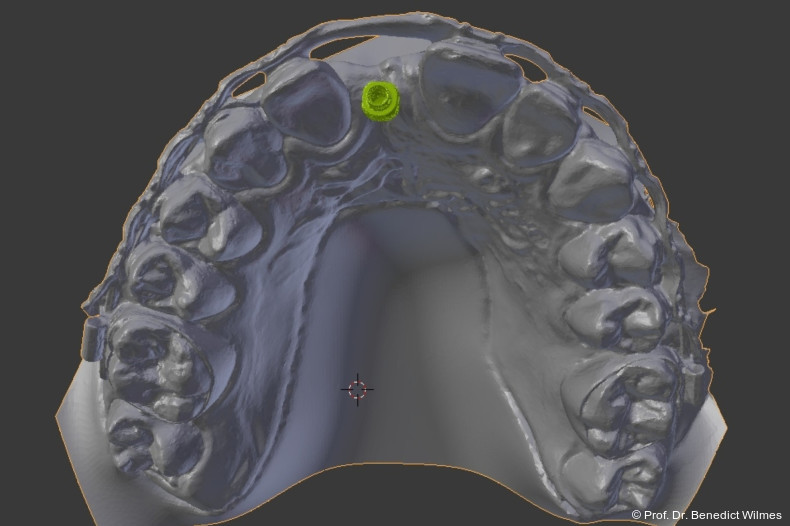

Die temporäre Versorgung eines fehlenden Oberkieferfrontzahnes beim Jugendlichen mit einem Miniimplantat stellt sich als eine sehr empfehlenswerte Therapiealternative zu Klebebrücke und Prothese dar. Die Ziele einer ästhetisch ansprechenden Interimsversorgung sowie eines Knochenerhalts können sehr gut mit dieser Methode erreicht werden. Dank neuer CAD/CAM-Techniken können die „Kinderimplantate“ heutzutage auch mit einem Insertionsguide nach dreidimensionaler Planung eingesetzt werden (Abb. 17–19).